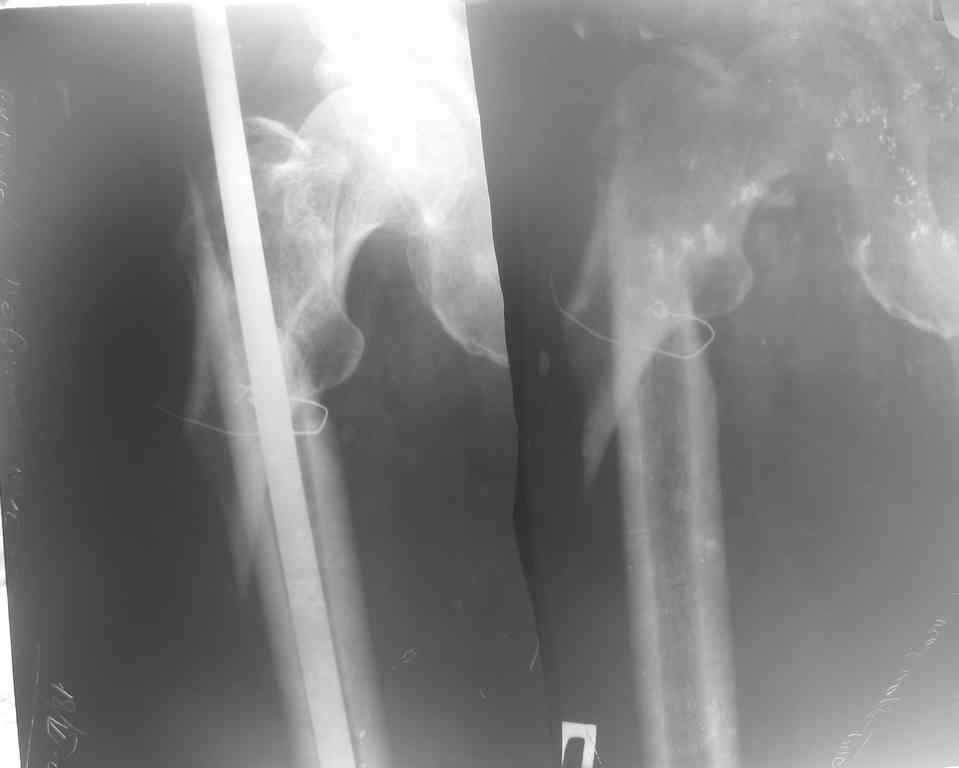

Несросщийся подвертельный перелом бедра

Глубокоуважаемые коллеги! Обратился больной 66 лет. Семь месяцев назад произведен неудачный интрамедуллярный остеосинтез штифтом Кюнчера в одном районе.

Через месяц штифт удалён, перелом несросся. Тактика лечения?

Причина удаления штифта - миграция, так как я думаю остеосинтез штифтом был произведен районным травматологом с нарушением техники остеосинтеза. Состояние мягких тканей в области перелома удовлетворительное. Клинические и биохимические анализы крови без патологии.